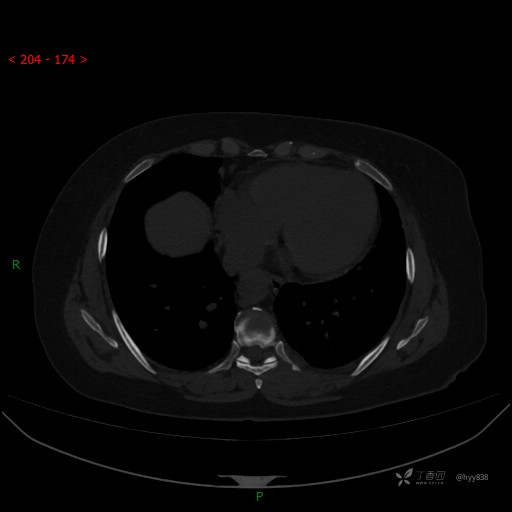

胸部CT平扫